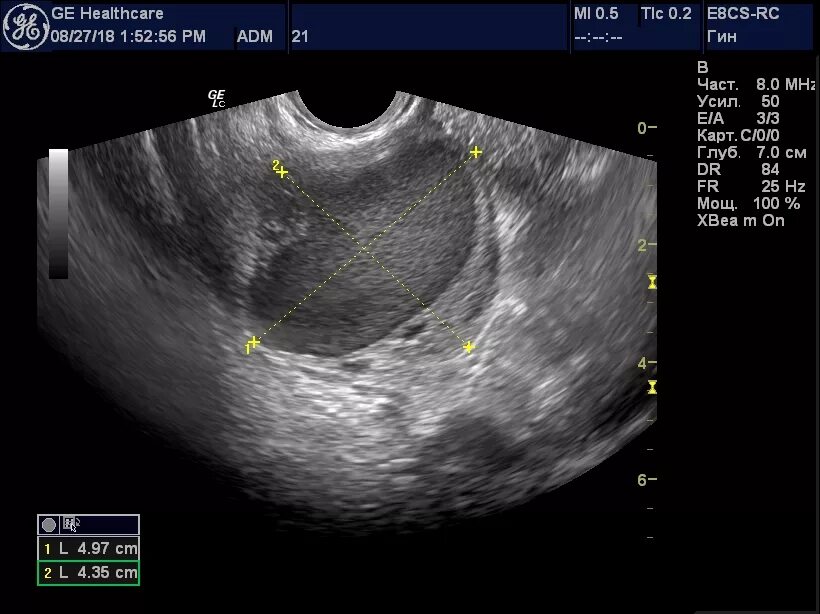

Киста уменьшается в размере